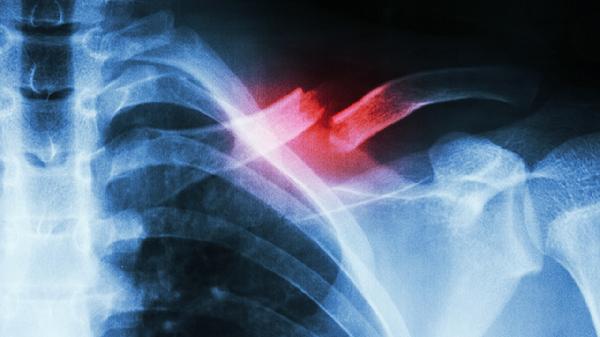

肋骨骨折了吃什么好得快 肋骨骨折多吃这些食物

肋骨骨折患者可以适量吃高蛋白食物、高钙食物、富含维生素D的食物、富含维生素C的食物、富含锌的食物等,也可以遵医嘱使用接骨七厘片、伤科接骨片、骨肽片、碳酸钙D3片、阿法骨化醇软胶囊等药物。建议及时就医,积极配合医生治疗,在医生的指导下服用合适的药物,并做好饮食调理。